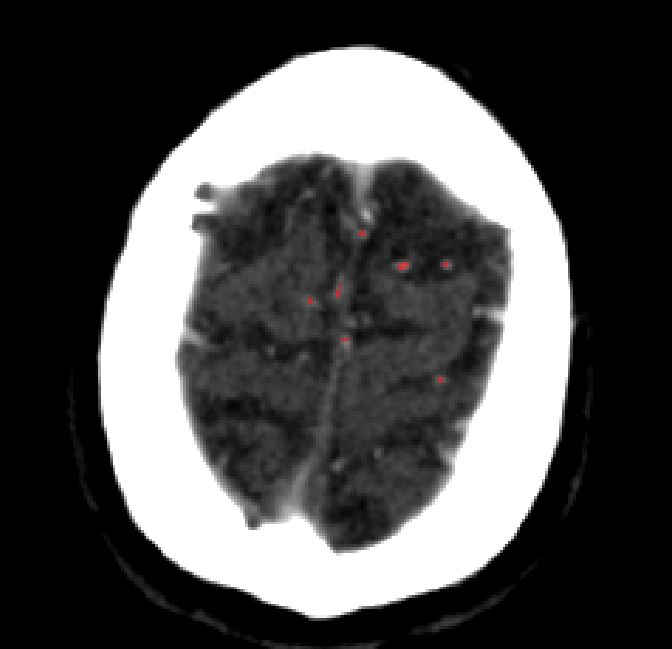

Refer to caption

Figure 4.4: Segmentations on regions near internal carotid arteries. Unaltered image (left). No pretrain model (mid-left). Fine-tuned model (mid-right). Hand-labeled ground truth (right).

In the other hand, it should be noted that fine-tuned models suffered from false positives more often than models with no pre-training. The fine-tuned models appeared to occasionally segment regions near the skull, which although similar in intensity to vessels, had no resemblance in terms of shape. Examples of this are seen in Figure 4.4 near the occipital bone and near the right temporal bone. Examples of oversegmentation were observed to happen commonly around the internal carotid arteries. This is likely due to the amount of contact surface between the artery and the surrounding bone. There was also a tendency for all model conditions to segment bone regions that were similar in shape to large vessels (Figures 4.3 and 4.4). Bone structures in such regions have similar pixel intensities to the arteries transporting contrast material, which could explain the source of confusion for a model.